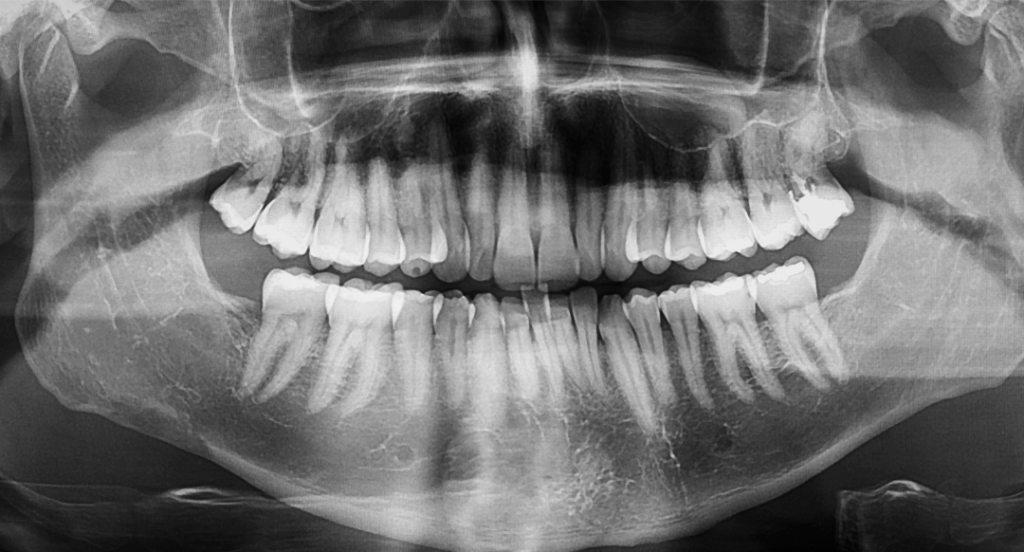

- Digital X-rays that capture current images of your teeth and bone structure

- 3D Dental Imaging (Cone Beam CT) when needed for an in-depth 3D view of hard and soft tissues

At our San Jose dental office, we pair the clinical exam with digital X-rays and, when needed, 3D dental imaging to see what’s hiding beneath the surface. Visual inspection plus advanced imaging? That combination gives us a remarkably detailed understanding of what’s happening in your mouth.

We’ve completely replaced traditional film X-rays with digital radiography at our San Jose office, and the benefits are substantial. Digital X-rays produce high-resolution images instantly. Dr. Manassra can pull them up on a chairside monitor and review findings with you in real time. No waiting for film to develop. The images can be enlarged, enhanced, and compared side by side with previous X-rays for precise analysis.

Here’s the big one though. Digital X-rays emit up to 80% less radiation than conventional film-based systems. Dental X-rays have always been considered safe, but we follow the ALARA principle (As Low As Reasonably Achievable) to minimize exposure for every patient. Especially children and pregnant women.

For more complex cases, we use 3D cone beam computed tomography (CBCT). It produces a detailed three-dimensional model of your teeth, jawbone, sinuses, and surrounding structures. This technology is invaluable for planning dental implant placement, evaluating impacted teeth, diagnosing jaw pathology, and assessing bone volume before procedures like bone grafting or sinus lifts.A CBCT scan takes only seconds. Seconds. And it provides information that flat, two-dimensional X-rays simply can’t capture. When planning an All-on-4 full arch restoration, for instance, Dr. Manassra uses 3D imaging to map the exact bone density and anatomy of your jaw. Implants get placed with millimeter-level precision. That level of planning directly translates to better outcomes and faster healing for you.

What is 3D dental imaging used for?

3D cone beam CT imaging creates a detailed three-dimensional model of your teeth, jawbone, and surrounding structures. It is used for planning dental implants, evaluating impacted wisdom teeth, assessing bone volume for grafting procedures, and diagnosing complex dental conditions that two-dimensional X-rays cannot fully reveal.